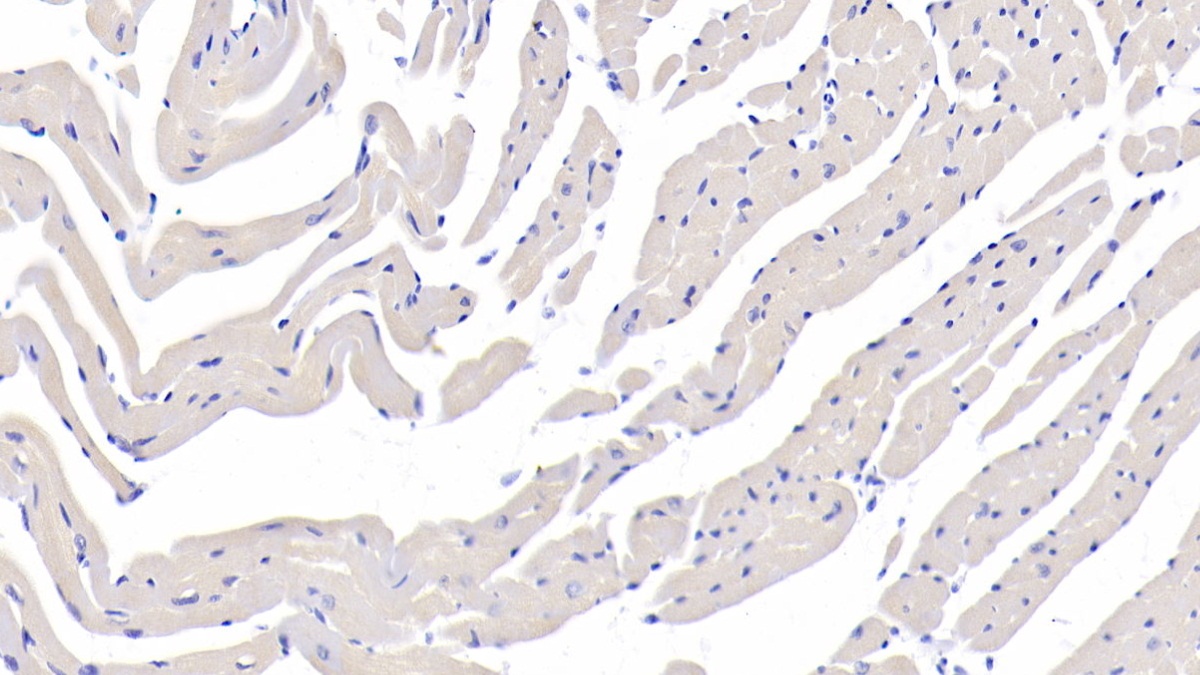

(單多株抗體)Fucosidase Alpha L1, Tissue (FUCa1) 多株抗體 (mouse)

抗體產品介紹: The antibody is a rabbit polyclonal antibody raised against FUCa1. It has been selected for its ability to recognize FUCa1 in immunohistochemical staining and western blotting. 抗體產品資料: FUCa1為多株抗體;免疫原FUCa1 (Asn185~Lys447)。可應用於Mus musculus (Mouse)之物種;host來源為Rabbit。此抗體經由Antigen-specific affinity chromatography純化,保存於PBS, pH7.4, containing 0.02% NaN3, 50% glycerol. 抗體濃度為200ug/ml,可應用於WB, ICC, IHC-P, IHC-F, ELISA等實驗,最佳實驗濃度請參考操作手冊。抗體之保存: 避免反覆冷凍解凍; 4°C保存;若需長期保存請貯存於-20°C。